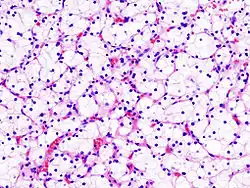

Микрофотография, демонстрирующая наиболее частый тип рака почки — светлоклеточный (окраска гематоксилином и эозином)

Светлоклеточный рак почки (микрофотография)